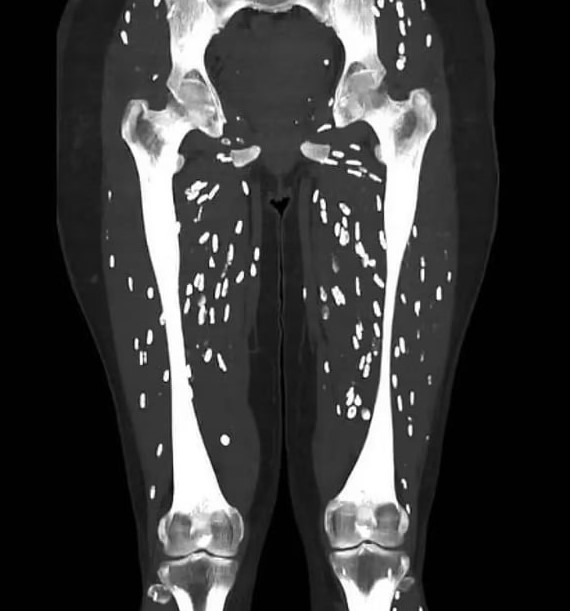

Hình ảnh bên trong cơ thể một người mắc sán dây lợn khiến nhiều người không khỏi hoang mang.

Tiến sĩ Sam Ghali, bác sĩ cấp cứu tại Đại học Florida (Mỹ) mới đây đã chia sẻ trường hợp nữ bệnh nhân mắc bệnh sán dây lợn. Bệnh này xuất hiện khi ấu trùng của loài sán dây xâm nhập vào các mô như cơ hoặc thậm chí là não. Thông qua việc chụp cắt lớp, có thể thấy chúng ký sinh trong cơ thể với hình dáng như những hạt gạo màu trắng.

Sán làm tổ khắp người, tất cả do một kiểu nấu thịt lợn nhiều người Việt thường xuyên mắc phải- Ảnh 1.

Hình ảnh bác sĩ Sam Ghali chia sẻ